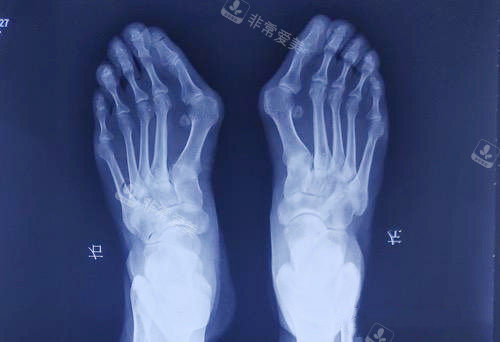

大脚骨外翻程度

苏敬达2026年定价逻辑以拇外翻角(HVA角)跖骨间角(IMA角)为核心测量指标,实现病情与费用的精又准匹配。

大脚骨X光片

包含项目:术前足部X光片/CT检查、手术操作费、基础麻醉费、1-3天住院观察费、术后初次换药费、基础改善指导。